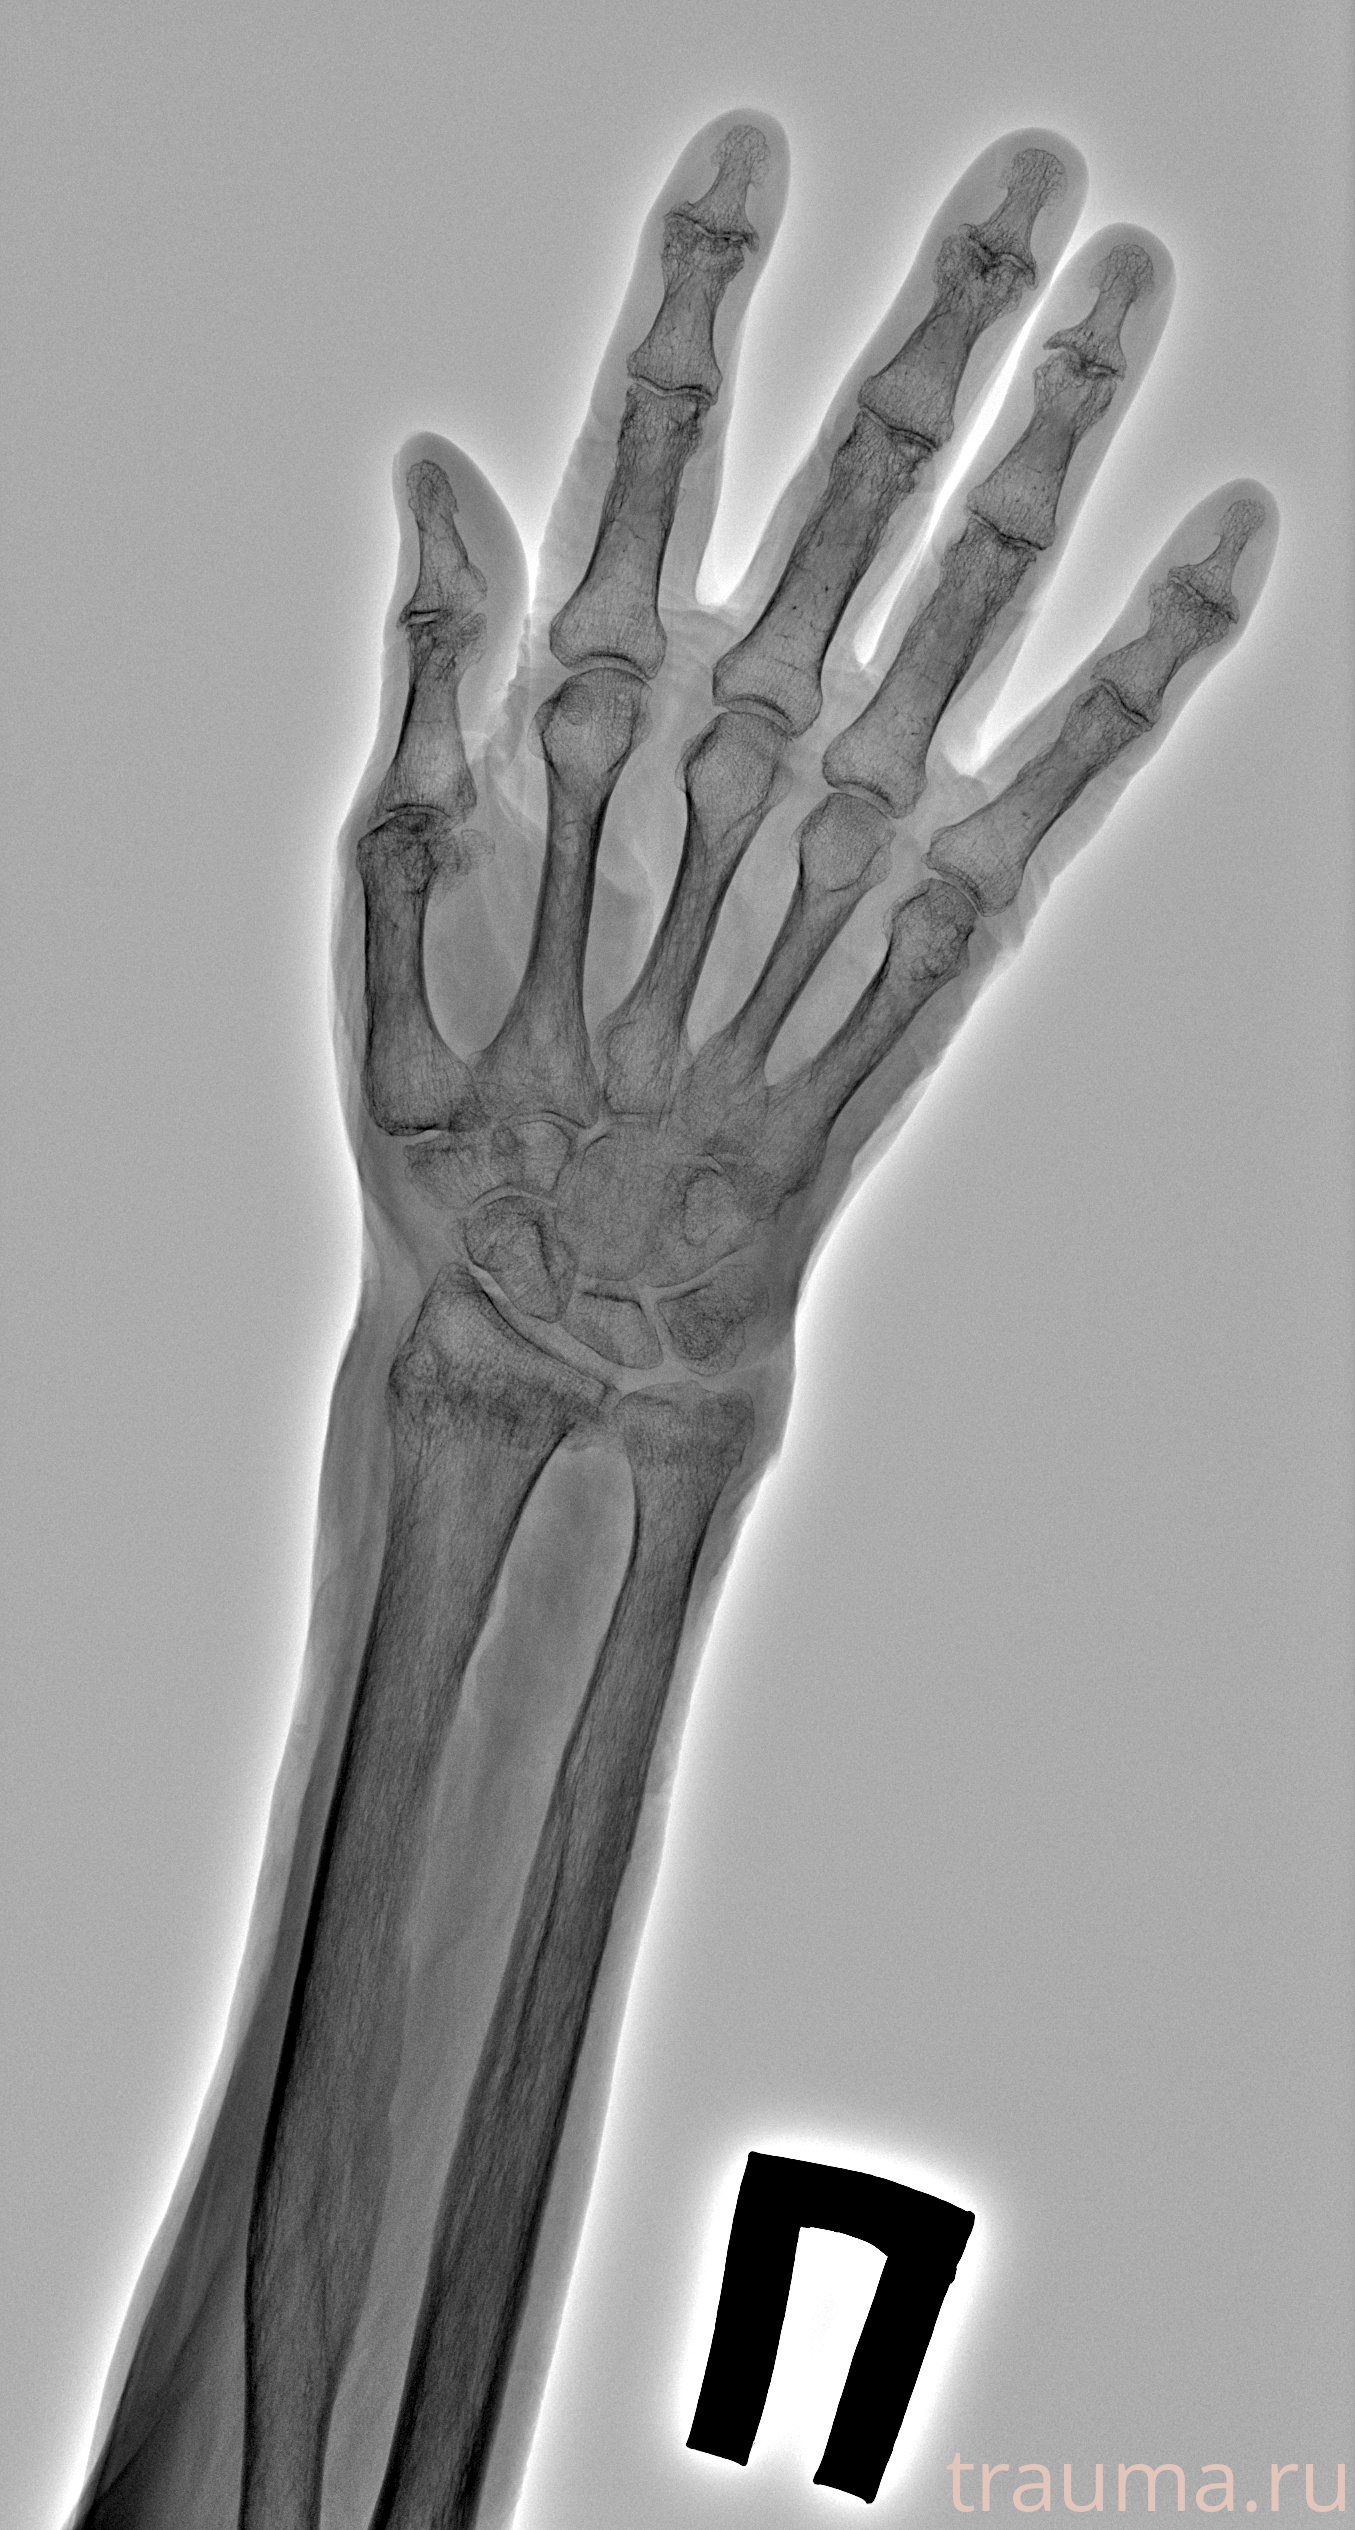

Перелом 3-5 ребер слева